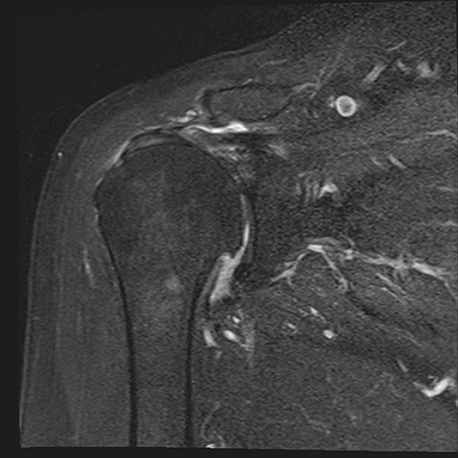

Normalmente o diagnóstico é feito através da radiografia (fig. 6) e tomografia computadorizada (para melhor determinar a versão da glenoide ou seu stock ósseo) (fig. 7) ou ressonância magnética (melhor avaliar integridade da coifa dos rotadores e infiltração gorda).